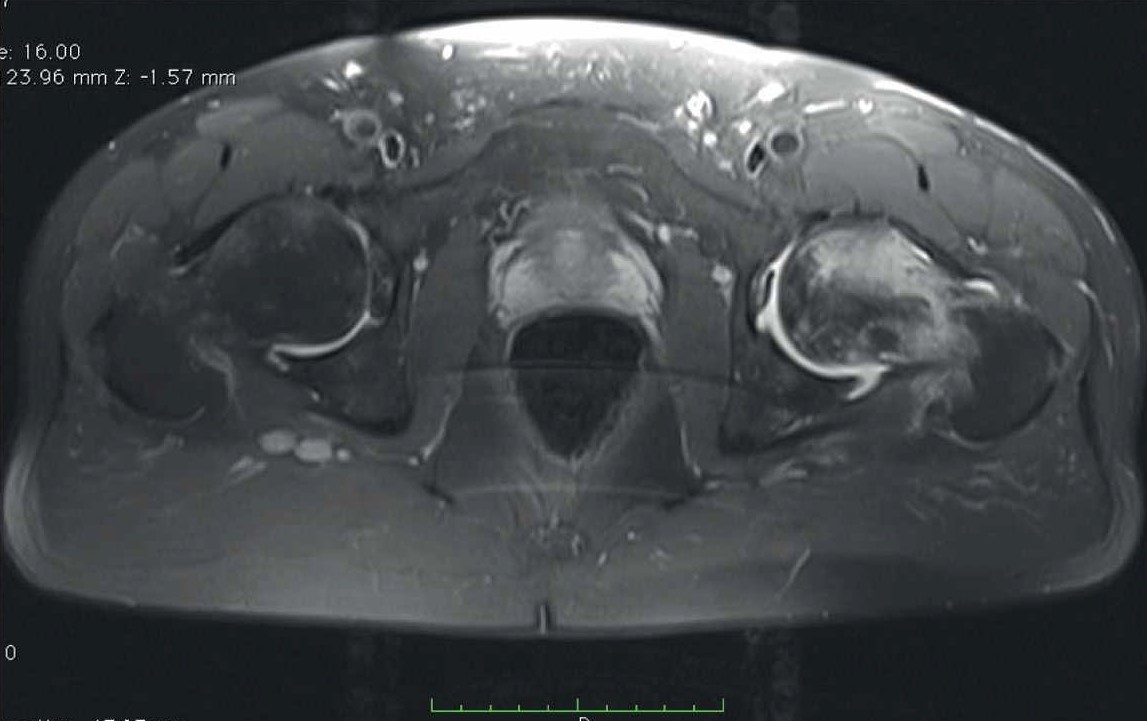

В декабре 2021 г. стала беспокоить боль распирающего характера в обоих тазобедренных суставах в покое, интенсивность боли снижалась при нагрузке, и в поясничном отделе позвоночника (6 баллов по ВАШ). Обратился к неврологу, и было начато консервативное лечение люмбалгии. В феврале 2022 г. вследствие неэффективности консервативного лечения и сохранения болевого синдром выполнена СКТ таза. Обнаружены двусторонний коксартроз, асептический некроз головок бедренных костей (рис. 3).

Рис. 3. СКТ таза у пациента В. Диагноз – двусторонний коксартроз, асептический некроз головок бедренных костей.

В связи с наличием субхондрального перелома головки правой бедренной кости пациенту выполнено тотальное эндопротезирование правого тазобедренного сустава.

В позднем послеоперационном периоде пациент отмечал восстановление функции правой нижней конечности, отсутствие болевого синдрома (0 баллов по ВАШ) в правом тазобедренном суставе